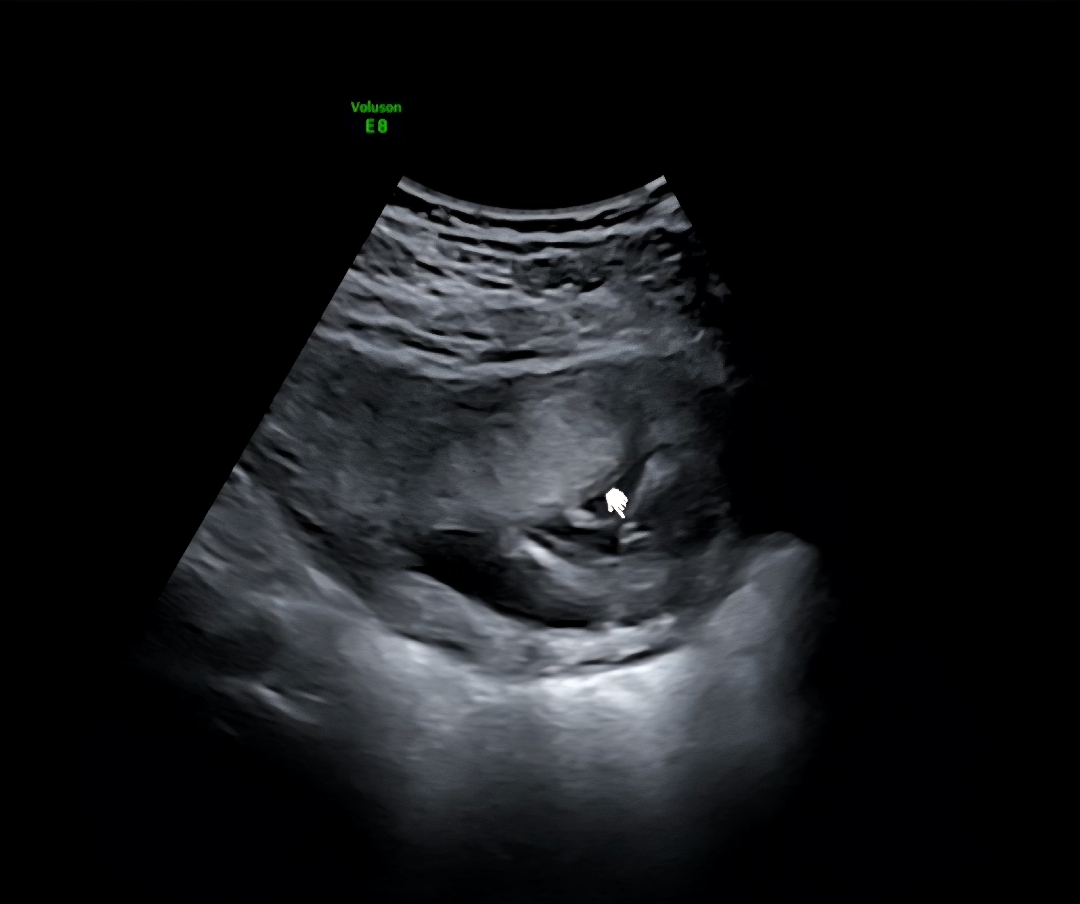

아들인가요??

엉덩이쪽에서 바라본 영상인데 아들일까요?ㅎㅎ